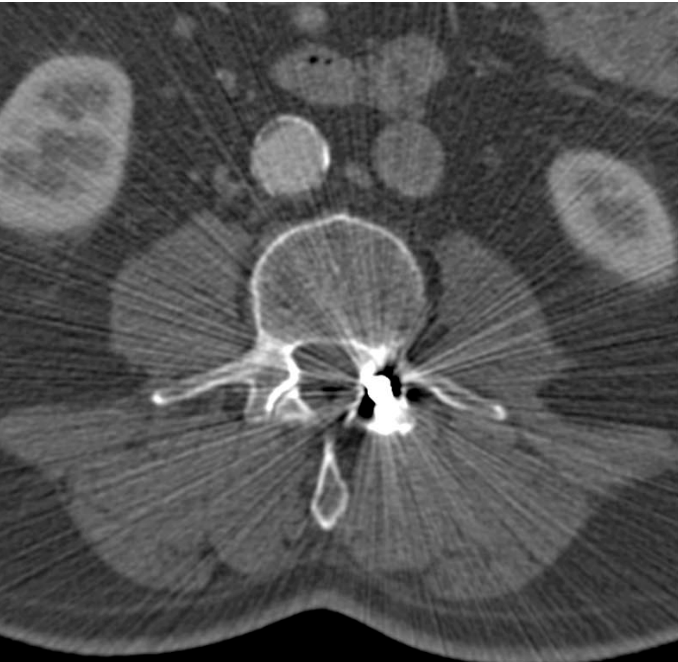

What is this artifact? How is it reduced?